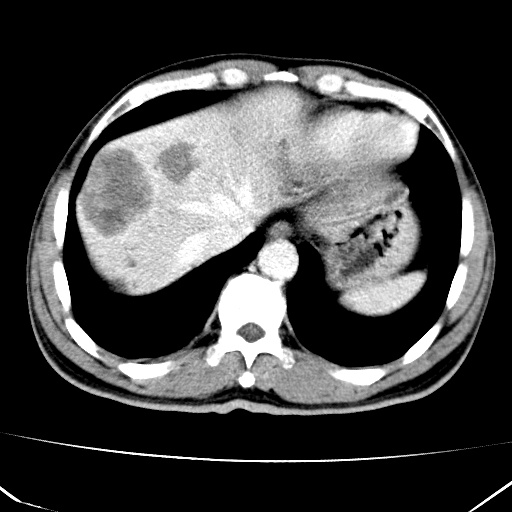

标题: CT17975:请求会诊。男、57岁。上腹部胀痛2天。临床诊断:糜 [打印本页]

标题: CT17975:请求会诊。男、57岁。上腹部胀痛2天。临床诊断:糜

肝脏多发类圆形低密度影,考虑肝脏转移瘤,肝胃韧带一淋巴结肿大,原发?胃癌?

考虑胃癌并肝脏及腹膜后淋巴结转移;不排除淋巴瘤。

肝内转移瘤,腹腔及腹膜后淋巴结转移。